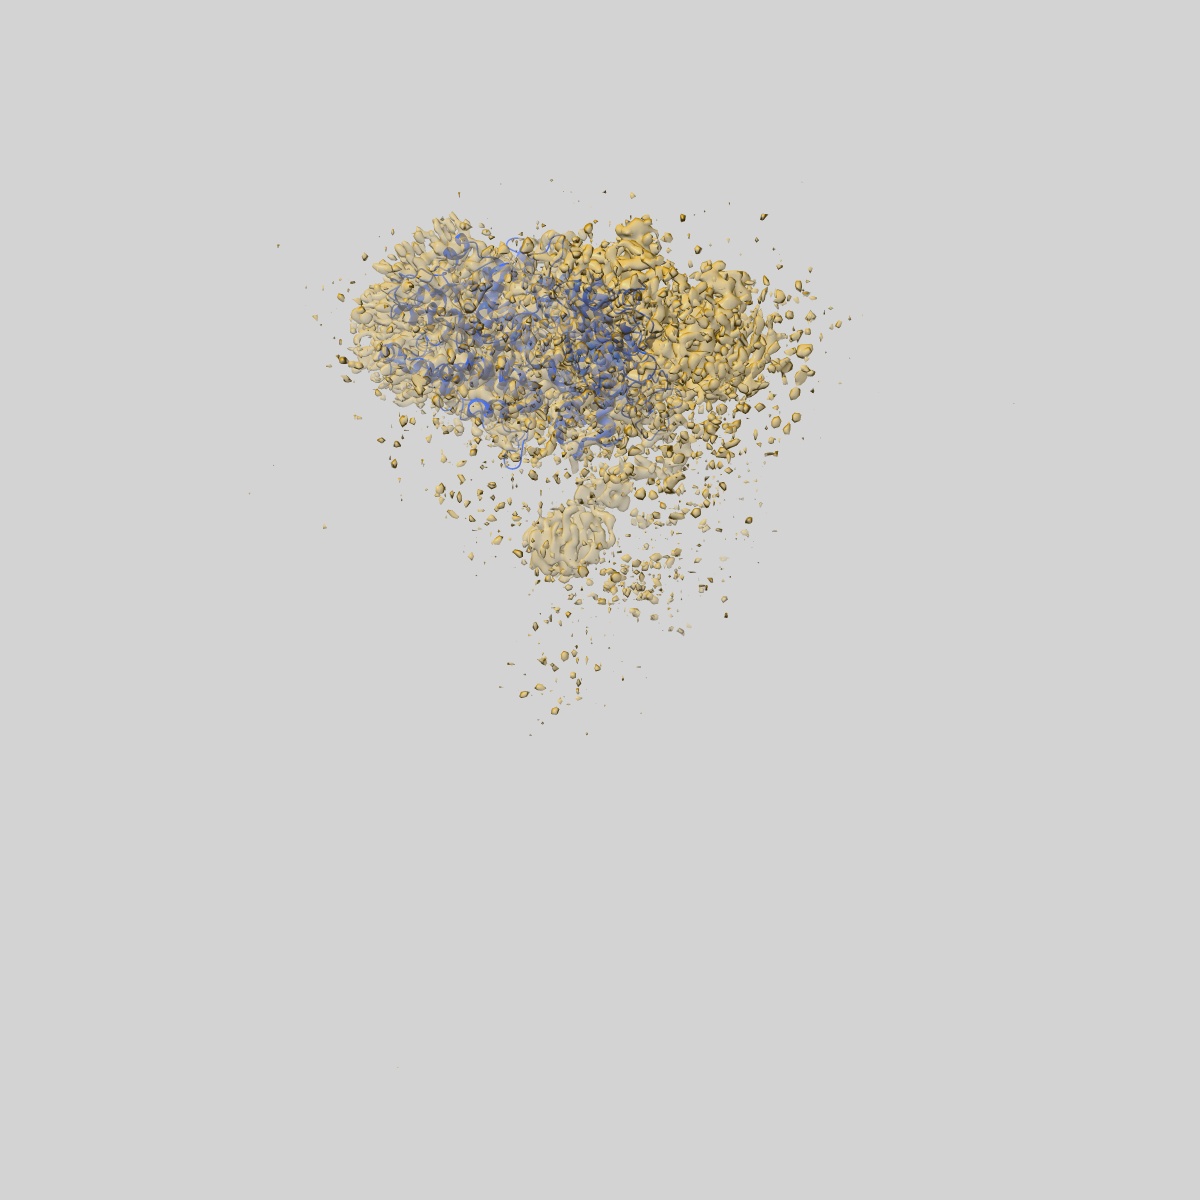

BA.1 SARS-CoV-2 Spike bound to mouse ACE2 (local)

Single-particle3.22 Å

Sample: SARS-COV2 BA1 bound to mouse ACE2

Fitted models: 8aqu

Cryo-EM structures and binding of mouse and human ACE2 to SARS-CoV-2 variants of concern indicate that mutations enabling immune escape could expand host range.